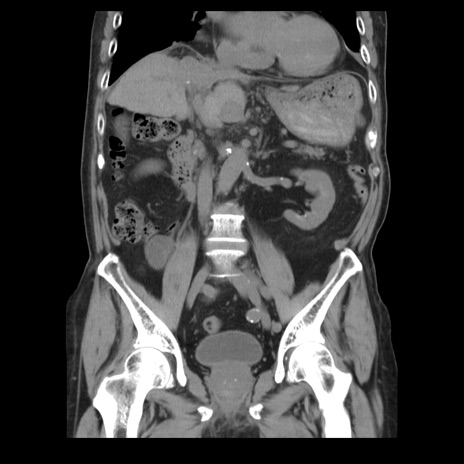

症例21(冠状断像)

【症例】70歳代男性

【主訴】腹痛

【現病歴】肝硬変・肝細胞癌にてかかりつけの方。約9時間前に食後より腹痛出現。症状が徐々に増悪し、嘔吐出現したため来院。

【既往歴】肝硬変、肝細胞癌(RFA、TACE後)

【身体所見】意識清明、表情苦悶様、BT 36℃、BP 129/78mmHg、P 88bpm、SpO2 97%(RA)、右上腹部から心窩部にかけて圧痛あり、反跳痛なし、筋性防御あり。

【データ】WBC 5800、CRP 0.16